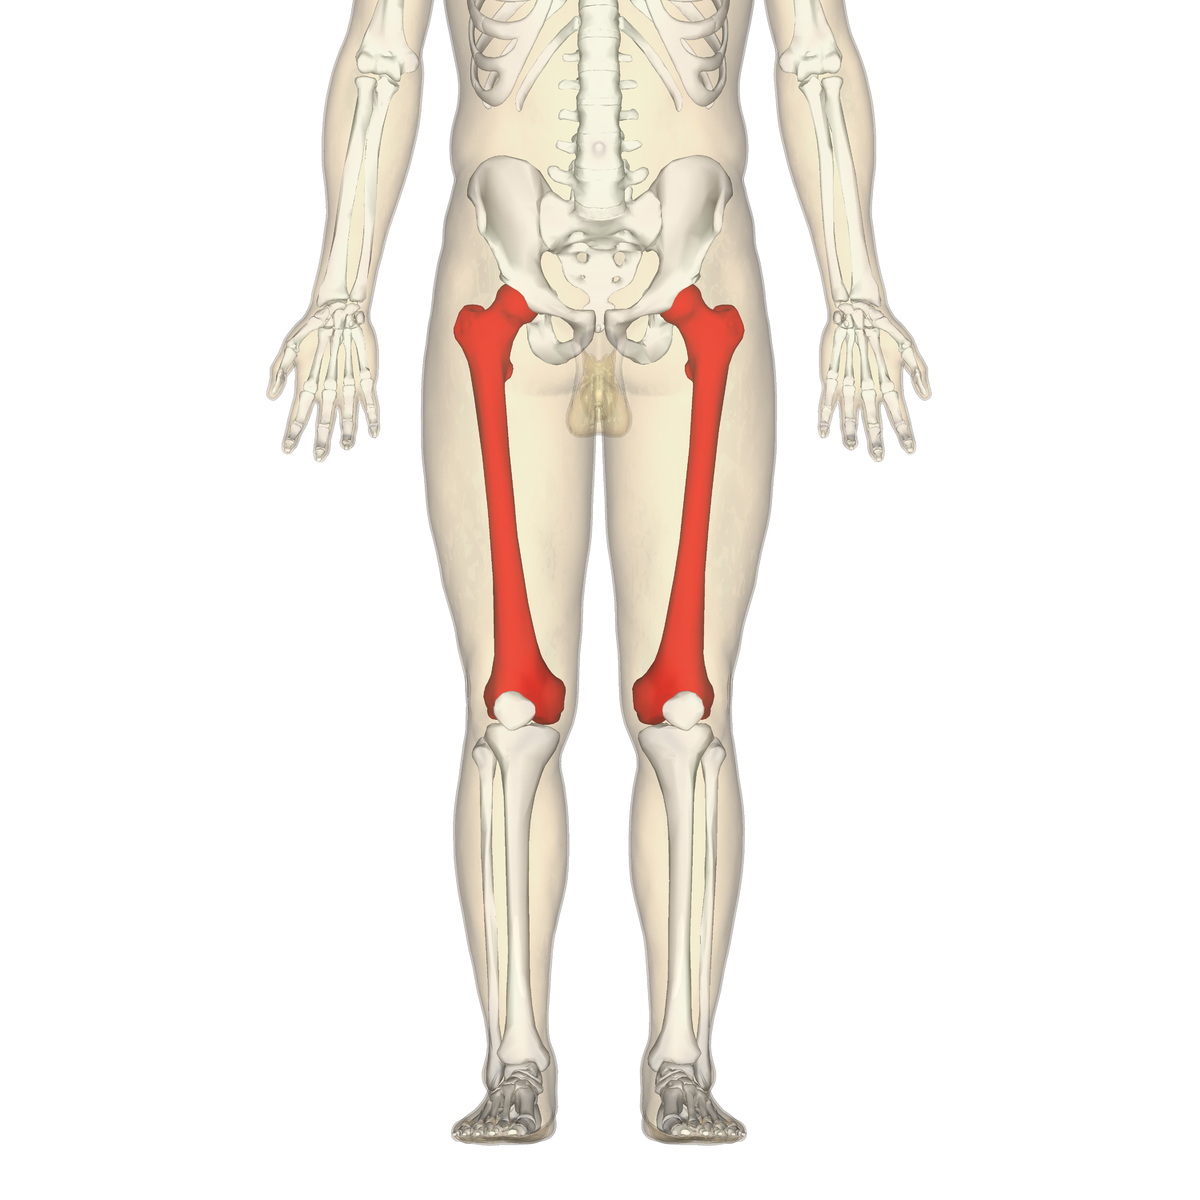

What is the femur?

The femur is the only bone in the thigh and acts to transmit forces from the tibia to the hip joint